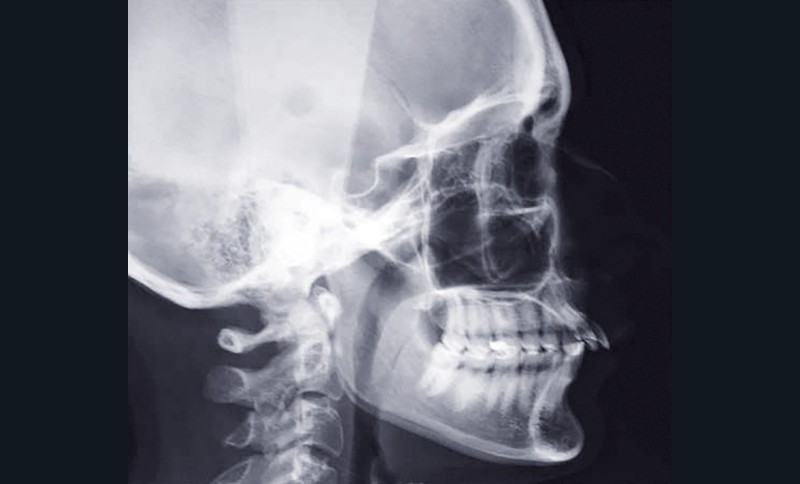

Charlotte présente donc une absence de 11, un surplomb et un recouvrement augmentés associés à une retromandibulie. La patiente a un profil convexe, hypodivergent avec une proalvéolie maxillaire et une classe II d’Angle. (fig. 1a à h). La radiographie panoramique confirme l’absence de 11 et la téléradiographique de profil, révèle une classe II squelettique (ANB : 6°, AoBo : 9 mm) par rétromandibulie ainsi qu’une proalvéolie maxillaire prononcée.

(I/Na : 40° I-Na : 7 mm) (fig. 2a et b).